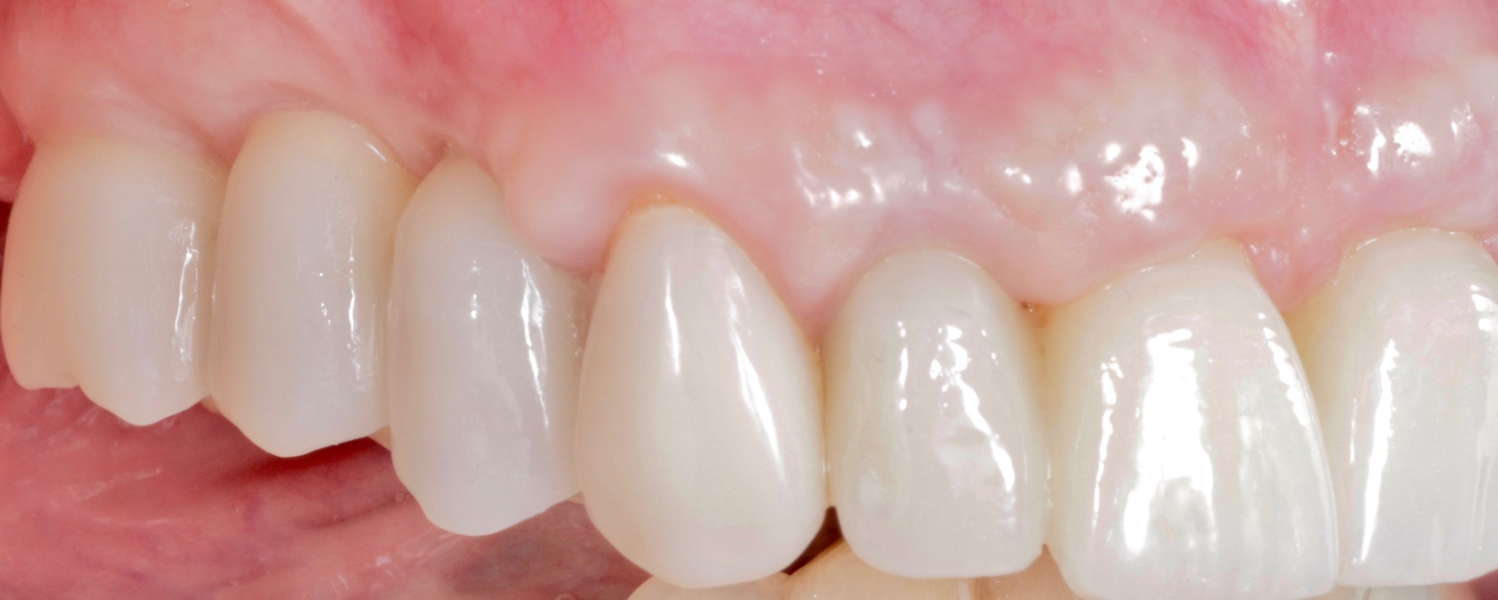

Definitive prosthetic treatment was performed after completion of implant healing with three CAD/CAM-fabricated monolithic zirconia bridges (DD cubeX2, Dental Direkt). The bridges were screwed on to BEGO titanium base abutments (Figs. 14–16). Good fit of the prosthetic superstructures was displayed in the radiograph after placement (Fig. 17). The two-year follow-up examination in July 2019 revealed excellent aesthetic and clinical soft-tissue conditions (Figs. 18–20). No radiographic bone loss had occurred at the implant sites (Fig. 21). Neither the submerged central incisors nor the distobuccal molar root displayed any signs of periapical inflammation, and the patient reported no complications. The patient’s oral hygiene had improved significantly during the follow-up period.

Fig. 14: Frontal aspect of the definitive prosthetic restorations, showing good aesthetic conditions with no signs of soft-tissue complications after insertion.

Fig. 15: Right lateral aspect of the restorations.

Fig. 16: Left lateral aspect of the restorations.

Fig. 18: Frontal aspect of the restorations after the two-year follow-up period.

Fig. 19: Right lateral aspect of the restorations after the two-year follow-up period

Fig. 20: Left lateral aspect of the restorations after the two-year follow-up period.